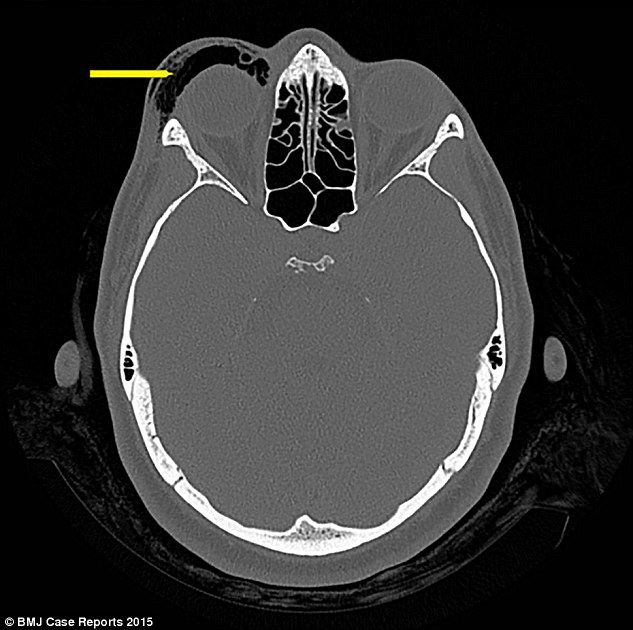

Vết sưng ngày càng lớn đồng thời cô gái cũng cảm thấy đau mắt. Các bác sĩ xác định, nguyên nhân của triệu chứng này không phải là sốt, viêm xoang hay tổn thương vật lý. Sau khi bệnh nhân nói đến việc xì mũi trước, các bác sĩ đã tìm ra nguyên nhân khiến mắt bị sưng là do khí tràn hốc mắt. Tình trạng này xảy ra khi không khí lọt vào các mô mềm xung quanh mắt.

Không khí lọt vào sẽ gây áp lực lên cấu trúc mắt, khiến các dây thần kinh thị giác bị chèn ép. Nếu không được điều trị kịp thời, bệnh nhân có thể bị mù. Ngoài ra, cô gái cũng bị gãy xương trong mũi. Các bác sĩ vẫn không dám chắc việc gãy xương mũi có phải do xì mũi quá mạnh hay chỉ đơn giản là một sự cố nhỏ.

Tuy nhiên, sự cố khí tràn hốc mắt lại khiến các bác sĩ vô cùng ngạc nhiên vì tình trạng này chỉ thường ấy khi bệnh nhân chịu một cú đấm mạnh vào mặt. Các bác sĩ cho biết, mắt sưng to là do khi tràn hốc mắt, thường xảy ra khi bị… đấm

Ảnh chụp đôi mắt sưng của người phụ nữ. Phía mắt phải có phần không khí tràn vào.